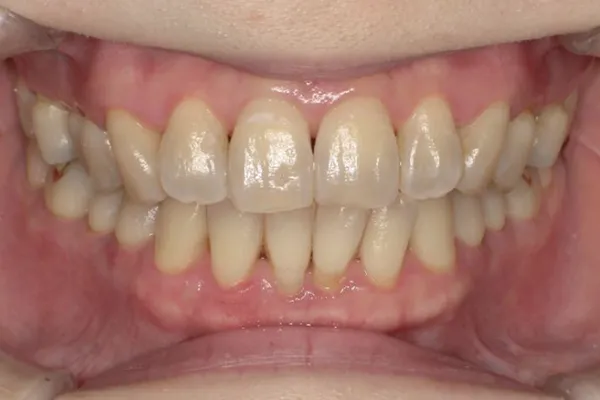

審美歯周病治療

見た目も美しく

歯周病治療を行うと歯茎が下がったとよく聞きます。残念ながら、炎症が長期に渡り存在していた歯茎や、重度歯周病では、治療を行うことにより歯茎が下がり炎症が除去されると歯茎が下がってしましやすいです。そういった場合、セラミックス治療を行うことで審美的に改善を図ることがあります。

また、歯周病はないのに、歯茎が下がってしまうことによる審美性が損なわれてしまう病気があります。そのような場合、歯茎の移植などを行うことにより、歯を削ることなく審美性を改善させることができます。 -